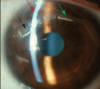

Qual a clínica da degeneração marginal de Terrien?

Afilamento corneano paracentral, com epitélio íntegro e poupando o limbo

Pannus atravessando a região de afilamento e depósito lipídico ao final da região de afilamento

Astigmatismo contra-a-regra

Fonte: AAO

Onde inicia o afilamento da degeneração marginal de Terrien?

Nasal superior, com progressão circunferencial